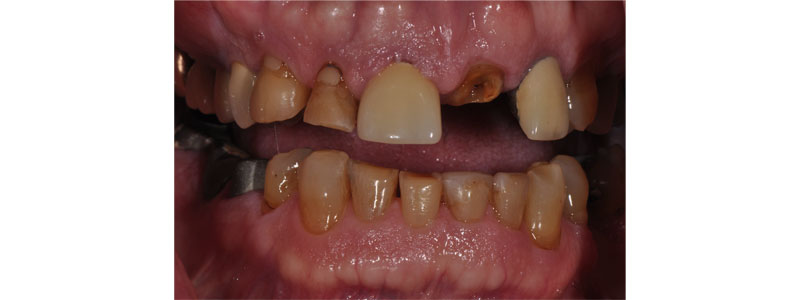

Images like this patient conjure up the fear and anxiety many dentists experience treating excessive tooth wear. Restoring worn dentitions is one of the more difficult undertakings dentists attempt. There is significant complexity involved in the restoration of these cases.